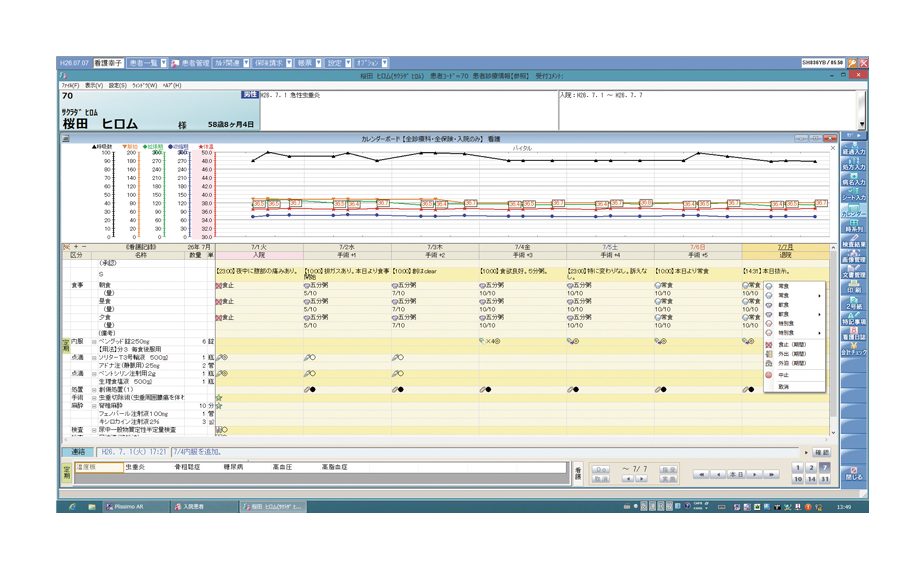

入院専用画面で、入院患者の情報を一元管理します。

入院受付や入院会計にも対応し、入院事務もスピーディーに処理します。